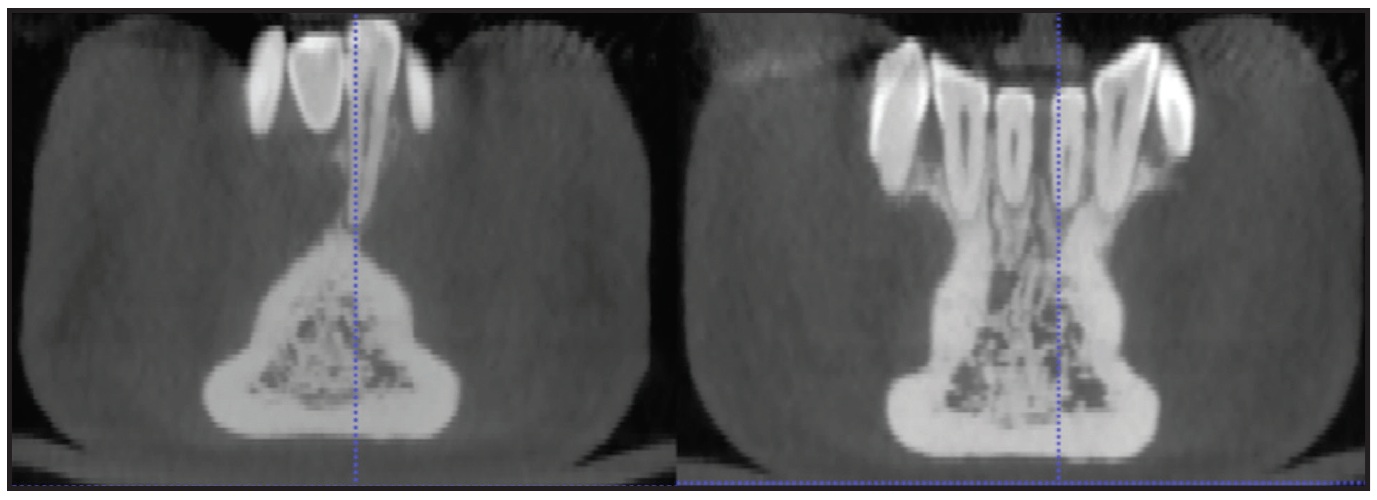

Fig. 6 Comparison of root positions before and after treatment.

The changes in torque were 10° for the lower left central incisor and 7° for the lower right central incisor (Fig. 7). The predicted changes were 12° and 10°, respectively, confirming that the virtual 3D model simulation of the final root positions was accurate.

Fig. 7 Changes in torque for lower left central incisor (A) and lower right central incisor (B) during clear aligner treatment.